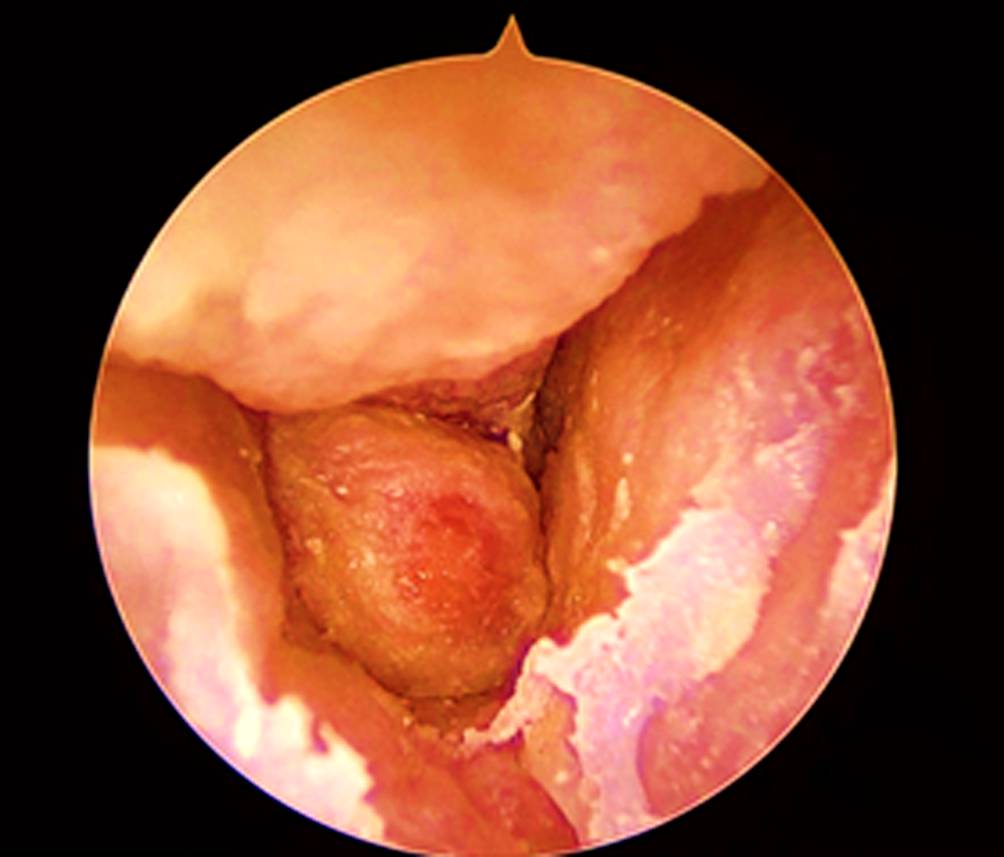

Ein 80-jähriger Patient stellte sich mit einer neu aufgetretenen peripheren Fazialisparese links sowie seit einer Woche bestehenden, intensiven, linksseitigen Kopfschmerzen und putrider Otorrhö Otorrhö vor. Otoskopisch zeigte sich ein geröteter Gehörgang mit nahezu vollständig verlegendem Granulationsgewebe vor dem Trommelfell (Abb. 1). Vor dem Hintergrund eines bekannten Typ-2-Diabetes mellitus mit inadäquater Stoffwechseleinstellung (HbA1c 8,1 %) ergab sich der klinische Verdacht auf eine Otitis externa necroticans (OEN). Ein mikrobiologischer Abstrich wurde entnommen, außerdem erfolgte eine hochauflösende Computertomographie (CT) des Felsenbeins. Diese zeigte nekrotische Arrosionen des Gehörgangsbodens und des vorderen Mastoids (Abb. 2). Aufgrund der bereits eingetretenen Hirnnervenbeteiligung wurde eine Mastoidektomie durchgeführt sowie eine systemische antibiotische Therapie mit Ceftazidim begonnen. Zusätzlich erfolgte eine topische Behandlung mit ciprofloxacinhaltigen Ohrentropfen und eine intensivierte diabetologische Mitbetreuung. Im mikrobiologischen Abstrich wurde ein auf die eingeleitete Therapie sensibler Pseudomonas aeruginosa nachgewiesen. Nach 14-tägiger i.v.-Therapie wurde der Patient in gebessertem Zustand mit oraler Fortführung (Levofloxacin) entlassen. Jedoch kam es 4 Wochen nach Entlassung zu einem Rezidiv mit erneuter Zunahme der Otorrhö und Schmerzsymptomatik. Eine weitere 2‑wöchige i.v.-Behandlung wurde erforderlich, gefolgt von einer 8‑wöchigen oralen Erhaltungstherapie. Der Patient blieb anschließend über 2 Jahre unter engmaschiger HNO-ärztlicher Kontrolle rezidivfrei.

Abb. 2

Felsenbein-Computertomographie (CT) bei Otitis externa necroticans bei einem 80-jährigen Mann mit a nekrotischer Zerstörung des vorderen Mastoids (offener, nicht ausgefüllter Pfeil), b,c entzündlicher Verlegung des äußeren Gehörgangs und nekrotischer Arrosion des unteren Randes (weißer Pfeil) sowie d luftgefülltem Paukenraum und Antrum (weißer Pfeil mit offener Spitze)